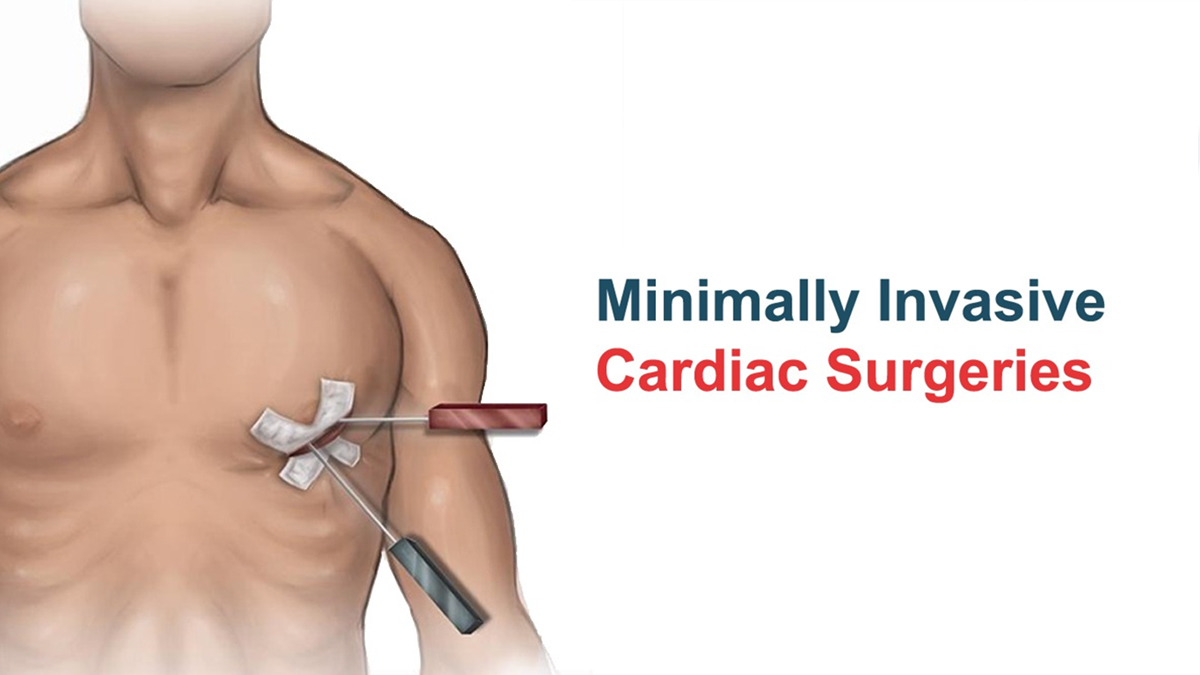

All You Need To Know About Minimally Invasive Cardiac,

All You Need To Know About Minimally Invasive Cardiac, Minimally Invasive Cardiac Surgery (MICS)-CABG - Yashoda,

Minimally Invasive Cardiac Surgery (MICS)-CABG - Yashoda, Dr M M YUSUF || One among the few minimally invasive and,